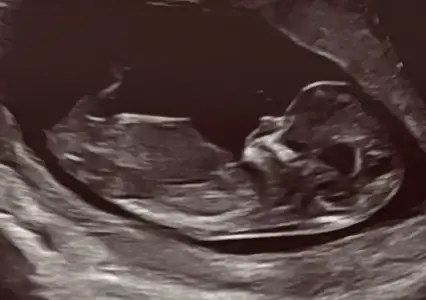

Kızlar bu ultrason görüntülerinden ben hiçbir şey anlayamıyorum, siz nasıl anlıyorsunuz ya 🙈 bunların açısı falan mı farklı olmalı anlayabilmek için, yoksa cinsiyet yorumu olan var mı? Chatgpt ye attım yorum yapmıyor, başka açıdan çekilmeli diyor. 12+0da çekildi bu görüntüler. Biz fetal dna yaptırdık ama yaptırdığımız yer yeditepe ünv hastanesi ve cinsiyet bilgisi paylaşmıyormuş. O yüzden oradan da öğrenemeyeceğim.

Ben kız diyorum çıkıntı olan yer daha yukarıda olsa erkek derdim bir de bacak arası gördüm sanki ve orası da boş :)